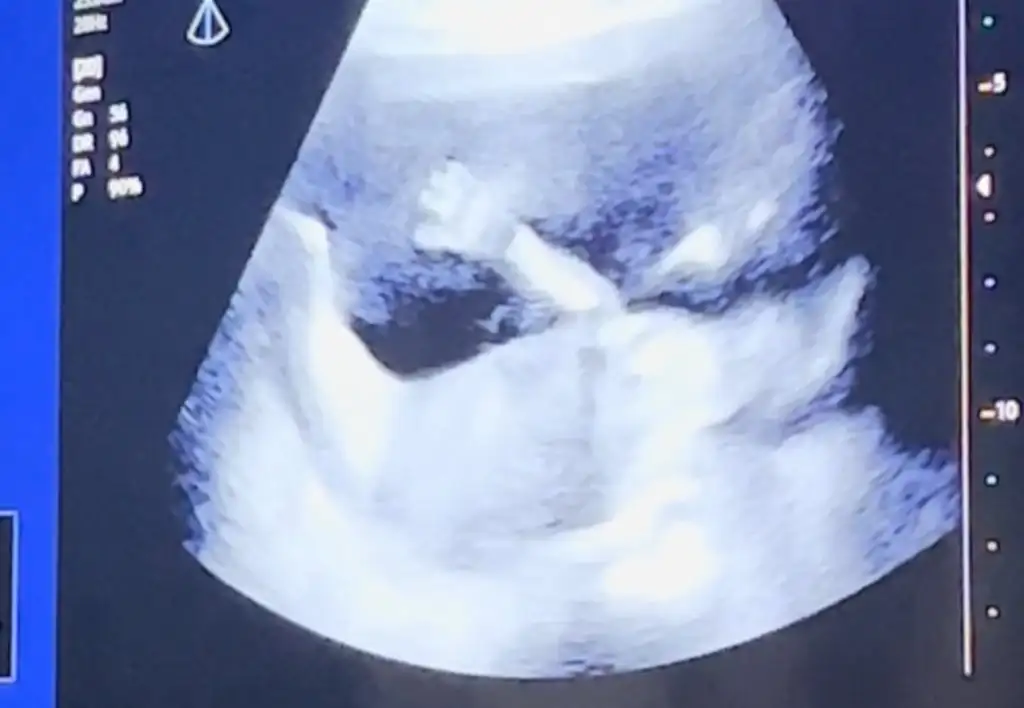

Selam teyzoşlar benim kızım yine şaşırtmadı ellerini gösterdi🥲 18 cm 223 gr olmuş tam olması gerektiği gibi her şey yolunda dedi doktorumuz 🙏🏻🥰

Ahh aynı benim kız eli kafasında❤️ çok muhteşem. ❤️🧿🌞 benim de 20 cm 220 gramdı baya baya aynıymışız😇